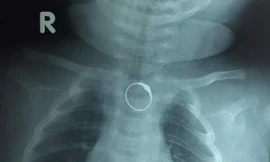

TPO - Bé gái 2 tháng tuổi được người nhà đeo cho chiếc nhẫn vàng ở ngón tay làm đồ trang sức. Tuy nhiên khi mút tay theo thói quen của trẻ mỗi khi đói, bé đã nuốt luôn chiếc nhẫn và phải nhập viện cấp cứu.